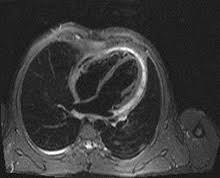

Die magnetresonanztomographie (mrt) spielt eine wichtige rolle für die diagnose. Vor allem störungen der pumpfunktion und der bewegungen der herzwand können genau untersucht werden. Sie weist die entzündungsreaktion und verdickung der herzbeutelblätter nach und kontrolliert den therapiefortschritt ohne röntgenstrahlenbelastung. Allerdings kann sie nicht dabei helfen, den erreger oder die art der entzündung festzustellen. Man findet örtlich im herzmuskel schwellungen, gewebszerstörungen oder vernarbungen. Ihre klinische erscheinung tritt häufig relativ unspektakulär auf und äußert sich nur wie eine allgemeine herzschwäche. Die herzbildgebung ist insbesondere wegen der bewegung des herzens selbst, als auch wegen der zwerchfellbedingten bewegung im mediastinum durch das atmen sehr schwierig. Je eingeschränkter die pumpfunktion ist, desto stärker ist die entzündung des herzmuskels. Allerdings kann sie auf niedrigem level auch unsichtbar sein. Die entzündungswerte im blut können ebenfalls aufschluss geben. Ein mrt des herzens ist vor allem dazu geeignet, die schwere der herzmuskelentzündung zu charakterisieren. Die schonung sollte solange beibehalten werden, bis der arzt wieder grünes licht gibt. Die besten anhaltspunkte für krankhafte vorgänge im herzmuskel liefert die kernspinuntersuchung.

Ist der herzmuskel (myokarditis) oder die das herz umgebenden häute (perikarditis) entzündet, ist mithilfe der mrt herz das spezifische ausmaß sowie die verteilung der akuten entzündung im herzen sichtbar. Nicht jede myokarditis (herzmuskelentzündung) muss behandelt werden. Die darstellung des herzens ist besonders schwierig, da es sich in vielen richtungen teils schnell bewegt. Herz mrt bei myokarditis (herzmuskelentzündung) mrt mit herzschrittmacher? Im vordergrund steht hier die körperliche schonung. Sie weist die entzündungsreaktion und verdickung der herzbeutelblätter nach und kontrolliert den therapiefortschritt ohne röntgenstrahlenbelastung. In den vergangenen jahren hat die untersuchung hierzu weiter an bedeutung zugenommen. Die entzündungswerte im blut können ebenfalls aufschluss geben. Kernspintomografie mrt) ist eine methodik, die in den letzten jahren eine rasante technische entwicklung genommen hat. Allerdings kann sie auf niedrigem level auch unsichtbar sein. In der akuten phase ist eine herzmuskelentzündung auch im mrt erkennbar, wasser im herzmuskel deutet auf eine entzündung hin. Es folgt eine messung von puls und blutdruck, um entwaige abweichungen festzustellen. Damit können schweregrad und heilungsaussichten einer herzmuskelentzündung beurteilt werden.